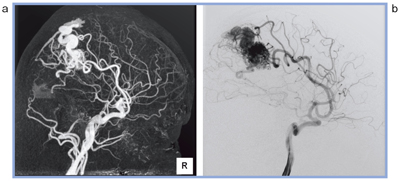

軌道同期ヘリカルスキャンは,単純と造影の軌道を同期させてヘリカルスキャンを行い,サブトラクション画像を再構成する技術である。軌道を同期させることにより,位置ズレのない良好なサブトラクション画像を得ることができ,ストリーク状アーチファクトを抑える効果も認められる。

脳動静脈奇形(AVM)の軌道同期サブトラクション画像と血管造影像とを比較してみても,遜色ない画質が得られている(図5)。

図5 軌道同期サブトラクション画像(a)と血管造影像(b)との比較